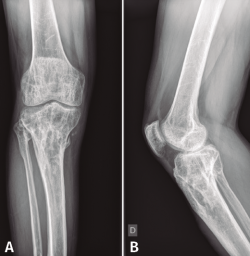

En el estudio radiológico posquirúrgico (Figura 4) se puede objetivar la resección ósea realizada.

Figura 4. Radiografías de frente y de perfil de tibia-peroné donde se objetiva la resección ósea realizada.